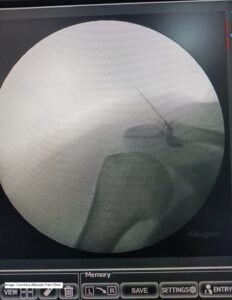

- Platelet-Rich Plasma (PRP) Injections : Patient undergoing Acromioclavicular joint -Platelet Rich Plasma Injection under fluoroscopy at Alleviate Pain Clinic. Image- Courtesy Alleviate Pain Clinic

PRP is derived from the patient’s blood and contains growth factors that can stimulate tissue healing and reduce pain and slow down the degenerative process of arthritis.These are administered under fluoroscopic or ultrasound guidance.